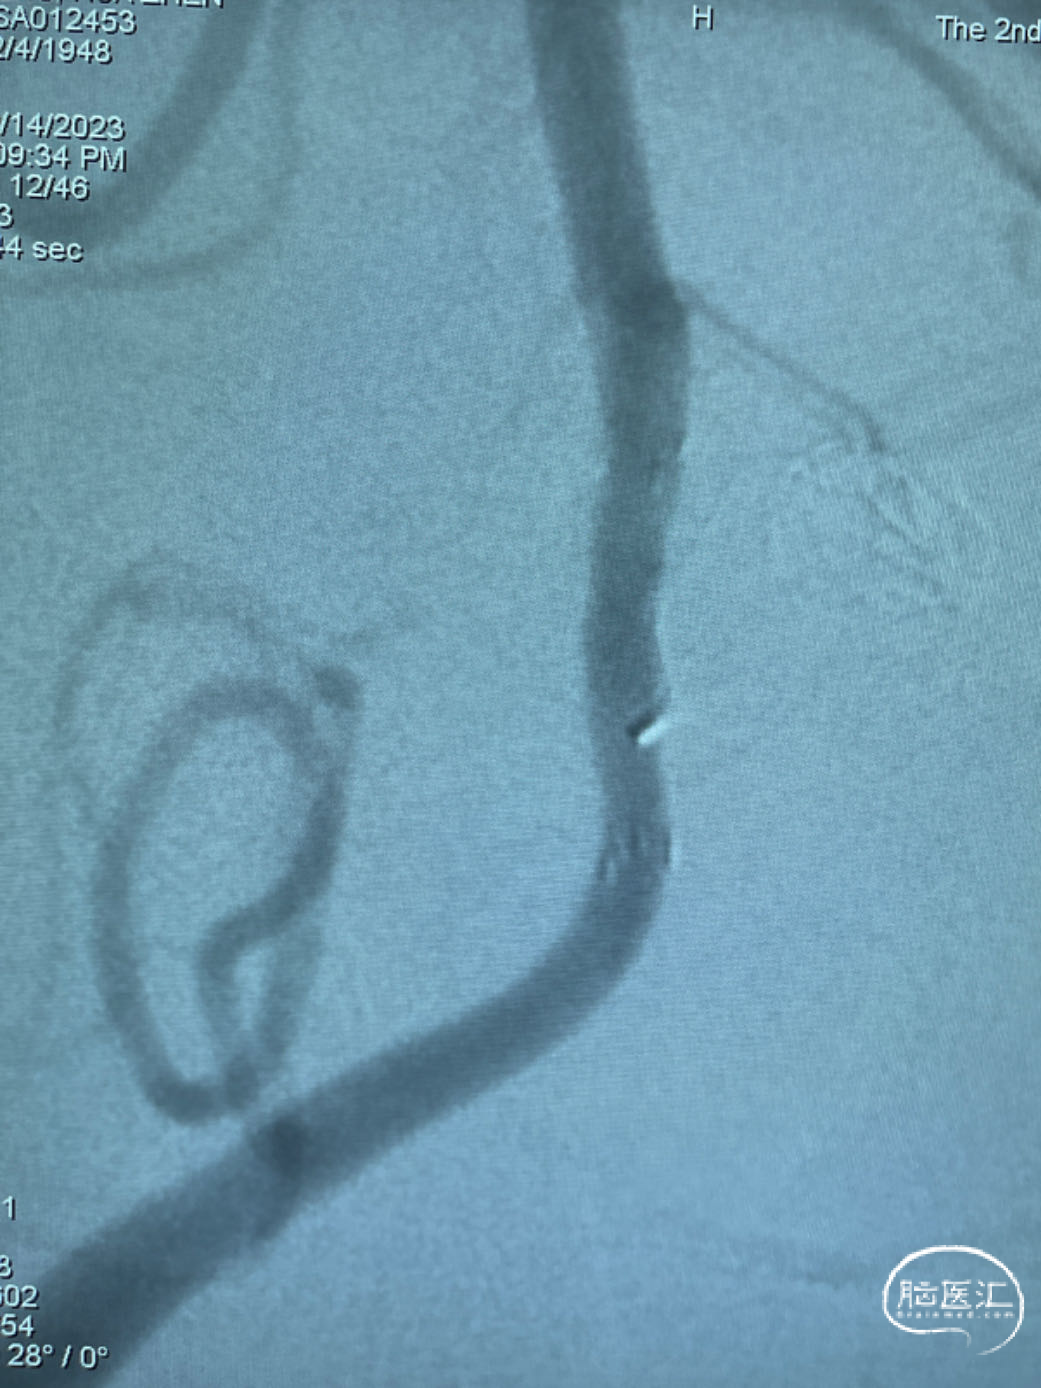

此为左侧大脑中动脉瘤,近端血管极为迂曲,瘤体有突出的子囊,动脉瘤与载瘤动脉有一定夹角,动脉瘤呈上窄下宽形状,M2段下干从瘤颈近端发出。

动脉瘤平均宽度5.41mm, 最小高度为3.71mm,瘤颈约为4.94mm,使用WEB™ SL 6*3mm瘤内扰流装置进行栓塞治疗。

释放WEB™:缓慢推出WEB™从种子至萌芽状态,继续向瘤腔内远端缓慢推送WEB™至萌芽至开花间状态;将WEB™和VIA™送至瘤顶,固定WEB™推送杆回撤VIA™,WEB™完全释放。

经造影可见WEB™尺寸合适,贴合瘤壁,覆盖瘤颈,且下支M2段分支及其他分支血管血流通畅。

解脱后,再次造影和Dyna-CT评估,可见动脉瘤瘤腔内有明显造影剂滞留,分支血管血流正常。